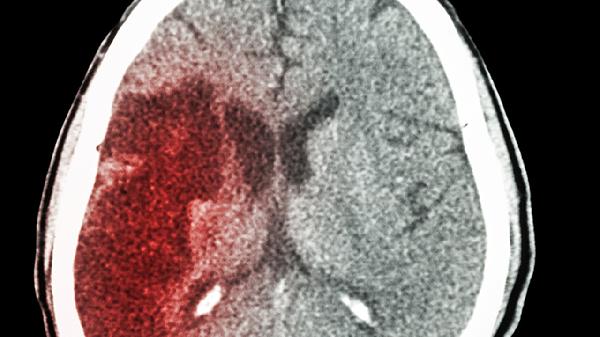

醒脑再造丸针对缺血性脑卒中恢复期出现的半身不遂、口眼歪斜等症状具有改善作用。这类患者多存在脑部供血不足导致的神经功能缺损,药物中的活血成分可帮助促进脑部微循环。使用期间需配合康复训练,并定期复查脑部影像学。忌食辛辣刺激食物,避免情绪激动。常见不良反应包括轻度胃肠不适,需在医生指导下调整用药。

五、血管性痴呆患者

由多发脑梗死或慢性脑缺血导致的血管性痴呆患者,在病情稳定期可服用醒脑再造丸改善注意力障碍、执行功能下降等症状。需先排除急性脑血管事件,控制好基础血管危险因素。建议联合认知康复训练,家属需监督用药并记录症状变化。严重肝肾功能不全者需减量,避免与含相同成分的中成药重复使用。